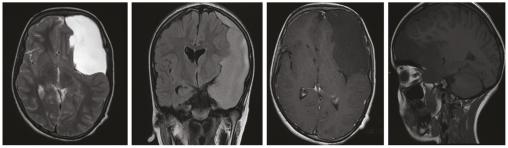

Un enfant de 12 ans est victime d’un traumatisme crânien minime occasionnant une diplopie. Le scanner cérébral montre deux hématomes sous-duraux hémisphériques chroniques ayant ressaigné et une volumineuse lésion kystique temporale gauche. Le patient a été opéré, avec évacuation de l’hématome sous-dural droit (fig. 1). Une imagerie par résonance magnétique (IRM) cérébrale a été réalisée pour mieux caractériser la formation kystique et pour le bilan étiologique du saignement ; elle montre une formation kystique extra-axiale temporale gauche renfermant un sédiment hémorragique en rapport avec un kyste arachnoïdien remanié, et un hématome sous-dural hémisphérique gauche d’allure plutôt chronique (fig. 2). Aucune autre malformation ne pouvait expliquer le saignement. Le diagnostic retenu est celui d’un kyste arachnoïdien remanié compliqué d’hématomes sous-duraux.